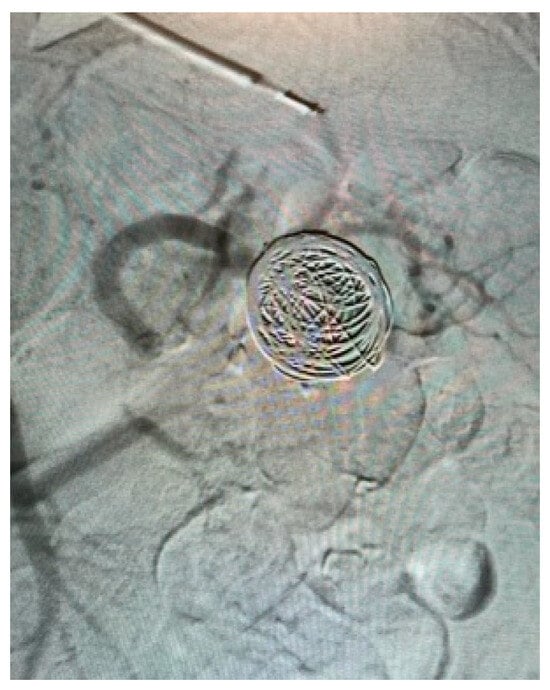

Appendix A.1. Clinical Case 1: Right Renal Visceral Arteriovenous Malformation